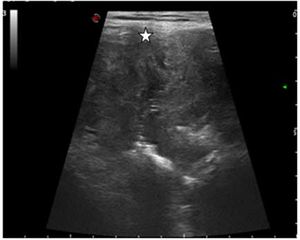

Case History: 20-year-old female was admitted with a two-month history of abdominal pain.